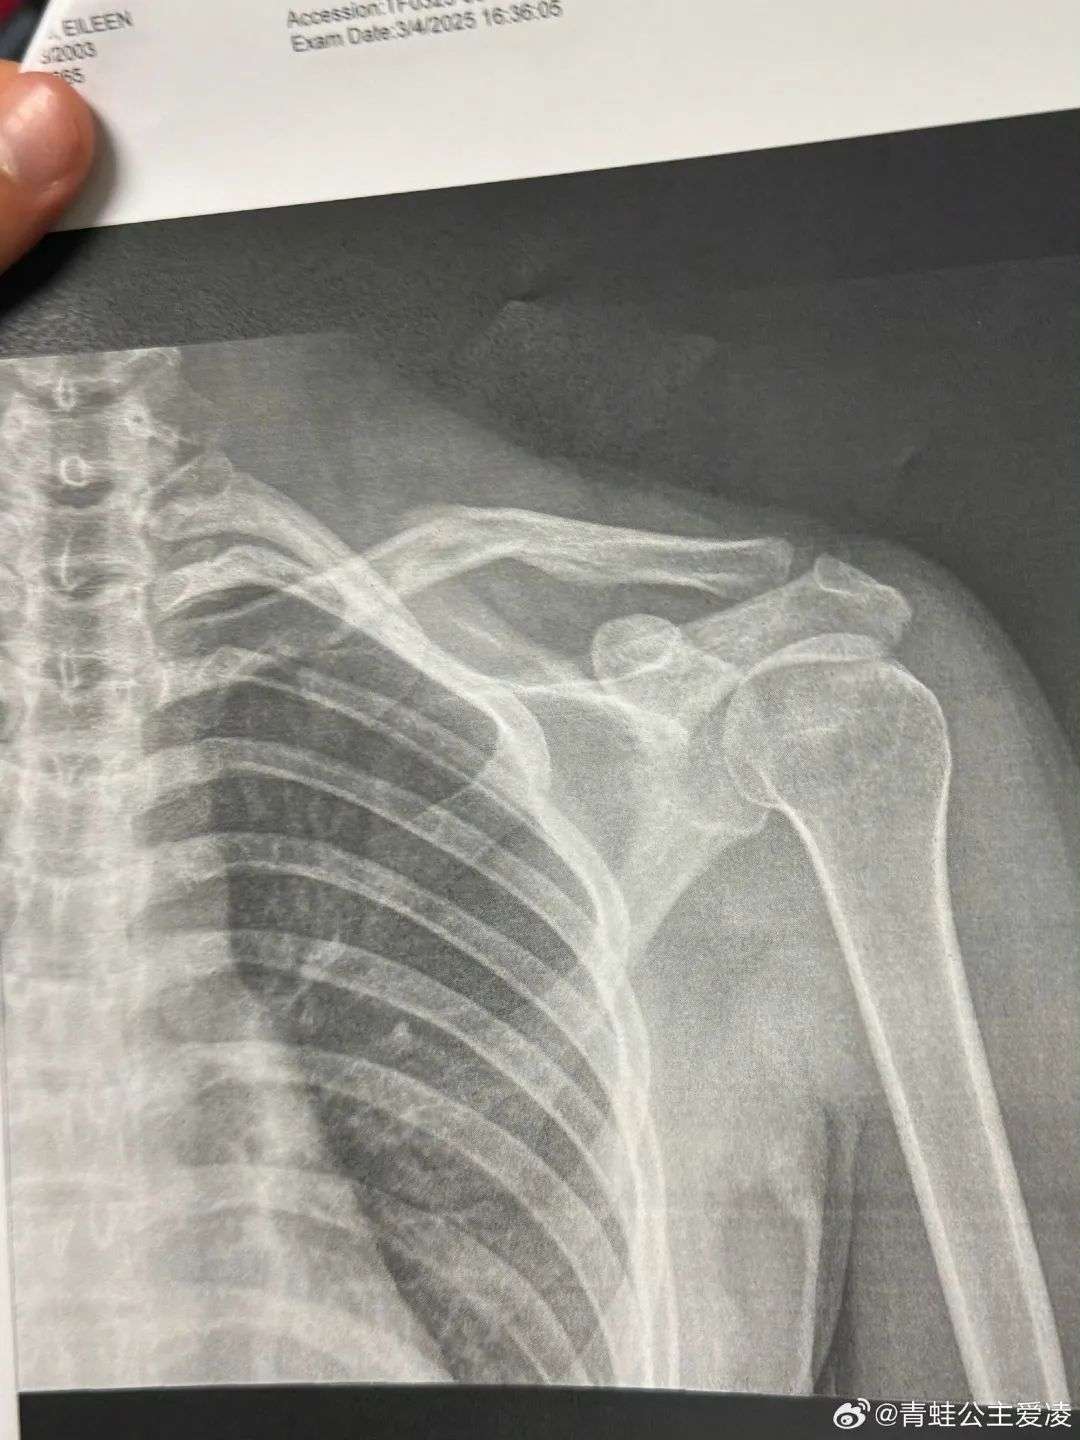

3月9日,她在社交媒体晒出肩部骨折的X光片,并配上心碎表情,引发粉丝广泛关注与祝福。